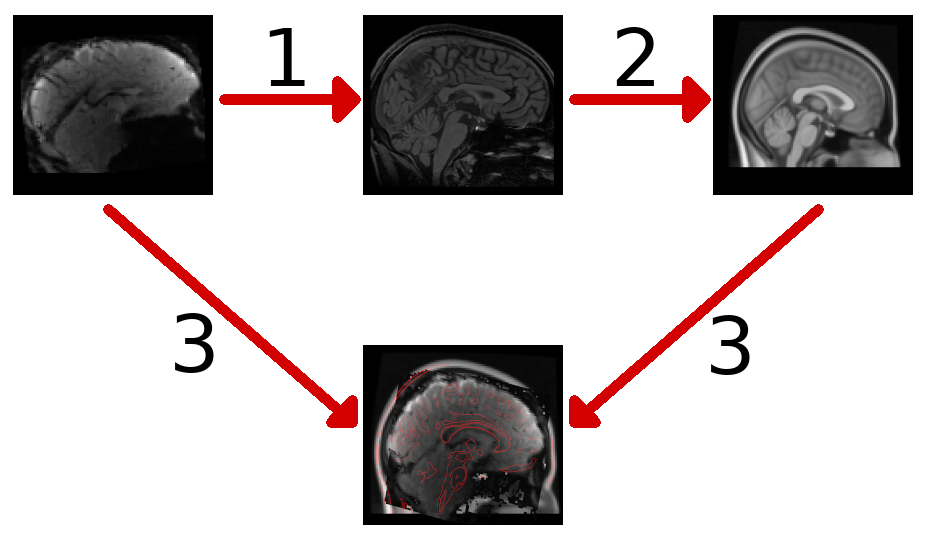

Once we have removed all of the noise from our data, we still need to do a few extra steps to get ready for the analysis. Most fMRI studies involve working with data from more than one participant. In order to combine data from different individuals, we need to align, or register the data so that they are anatomically aligned. These are automated processes which use sophisticated computational techniques to find a mapping between two images. We usually do this as follows:

- First we register an individual’s fMRI data to their structural image.

- Next, we register each individual’s structural image to a standardised average template image.

- Now we can combine both of the above steps to transform or project the fMRI data into the average template space.

Before we can perform these registration steps we need to run brain extraction on our structural image (remember that?). This is an automated process which identifies and removes non-brain regions from our structural image.

Once we have a brain-extracted structural image, we can register our functional images to the structural image, and then register the structural image to our standard template image.